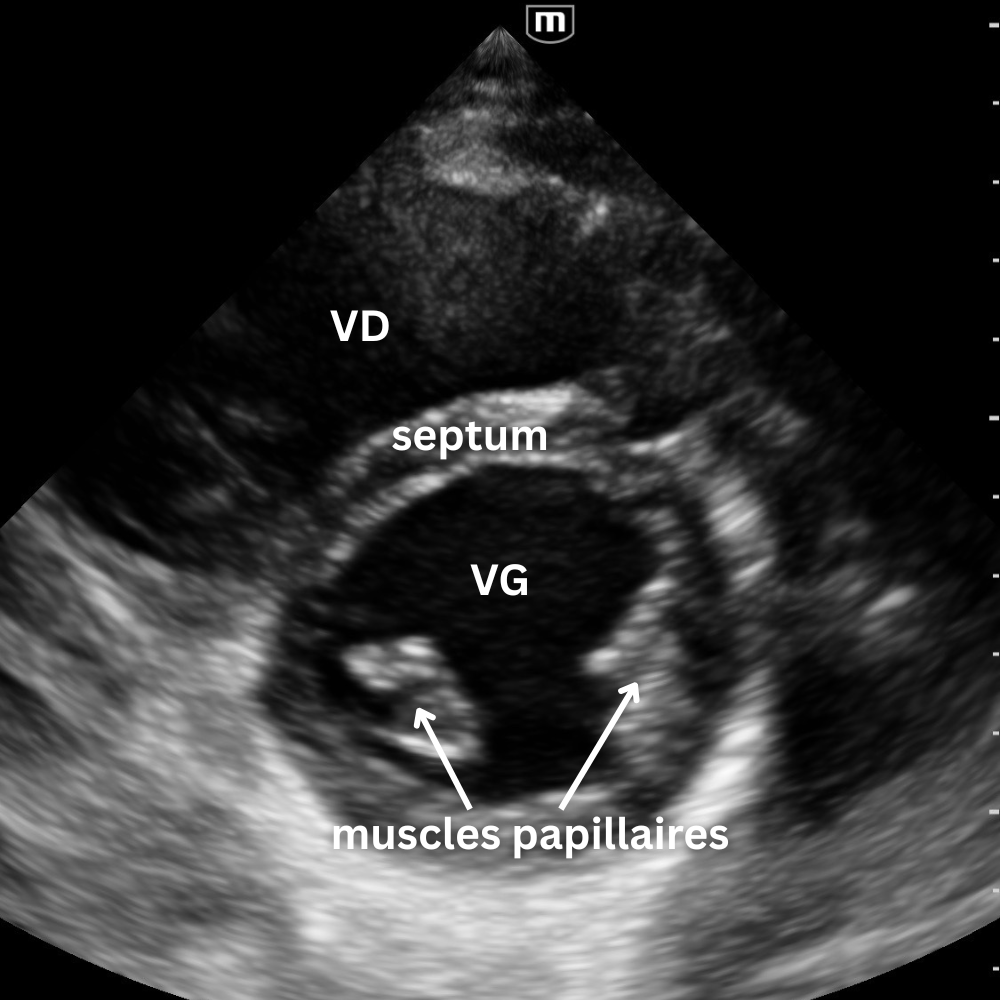

🔹 Vue Parasternale Petit Axe

→ La contraction est-elle harmonieuse ?

Même point d’appui que pour le parasternal grand axe, rotation à 90°, marqueur vers l’épaule gauche.

On observe la coupe circulaire du VG et du VD.

Un VG rond, contractile et homogène = fonction normale.

Un VG aplati ou en “D” = surcharge droite (embolie pulmonaire, HTP, tamponnade).

Une zone hypokinetique/akinetique = ischémie segmentaire.

Vue reine pour la fonction systolique et le septum interventriculaire.

Un léger mouvement de bascule permet d’explorer trois niveaux distincts :

- le plan de la valve mitrale

- le plan des muscles papillaires

- le plan de la valve aortique avec son aspect caractéristique en « signe Mercedes ».